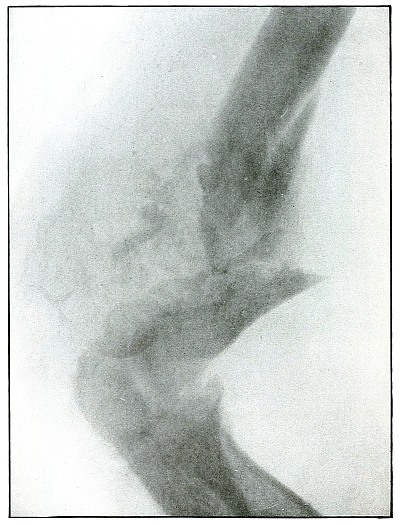

Plate 18.

[Pg 47]

Rifle—Plate 18.

UPPER EXTREMITY.

Gunshot Fracture of the Elbow,

without Injury to the Great Vessels and Nerves.

Wound of entrance, posterior to the external condyle.

Wound of exit, large laceration in front and above the internal condyle.

The wound is an example of the misnamed “explosive” action of a rifle

bullet. The force and direction of the missile, in high velocity,

split the bone into many fragments, and, transmitting its energy to

some of the fragments, carried them through the skin and caused the

large laceration at the point of exit by the simultaneous escape of

the bullet and fragments. The wound was so heavily infected, that a

cellulitis advanced to the shoulder and to the wrist to such extent

that the arm was marked by eminent surgical opinion for amputation.

Free incision, drainage, antisepsis and incidental removal of detached

fragments controlled the infection and brought about slow resolution.

After six months of careful treatment the wound was healed with an

ankylosed elbow with normal function of the forearm, except for

limited rotation.

Treatment indicated in such cases is always conservative. Infections

contraindicate any formal surgical interference. The dangers of

infection in such cases are to be risked to avoid amputation.

Results may be considered favorable even with elbow ankylosis.

[Pg 48]